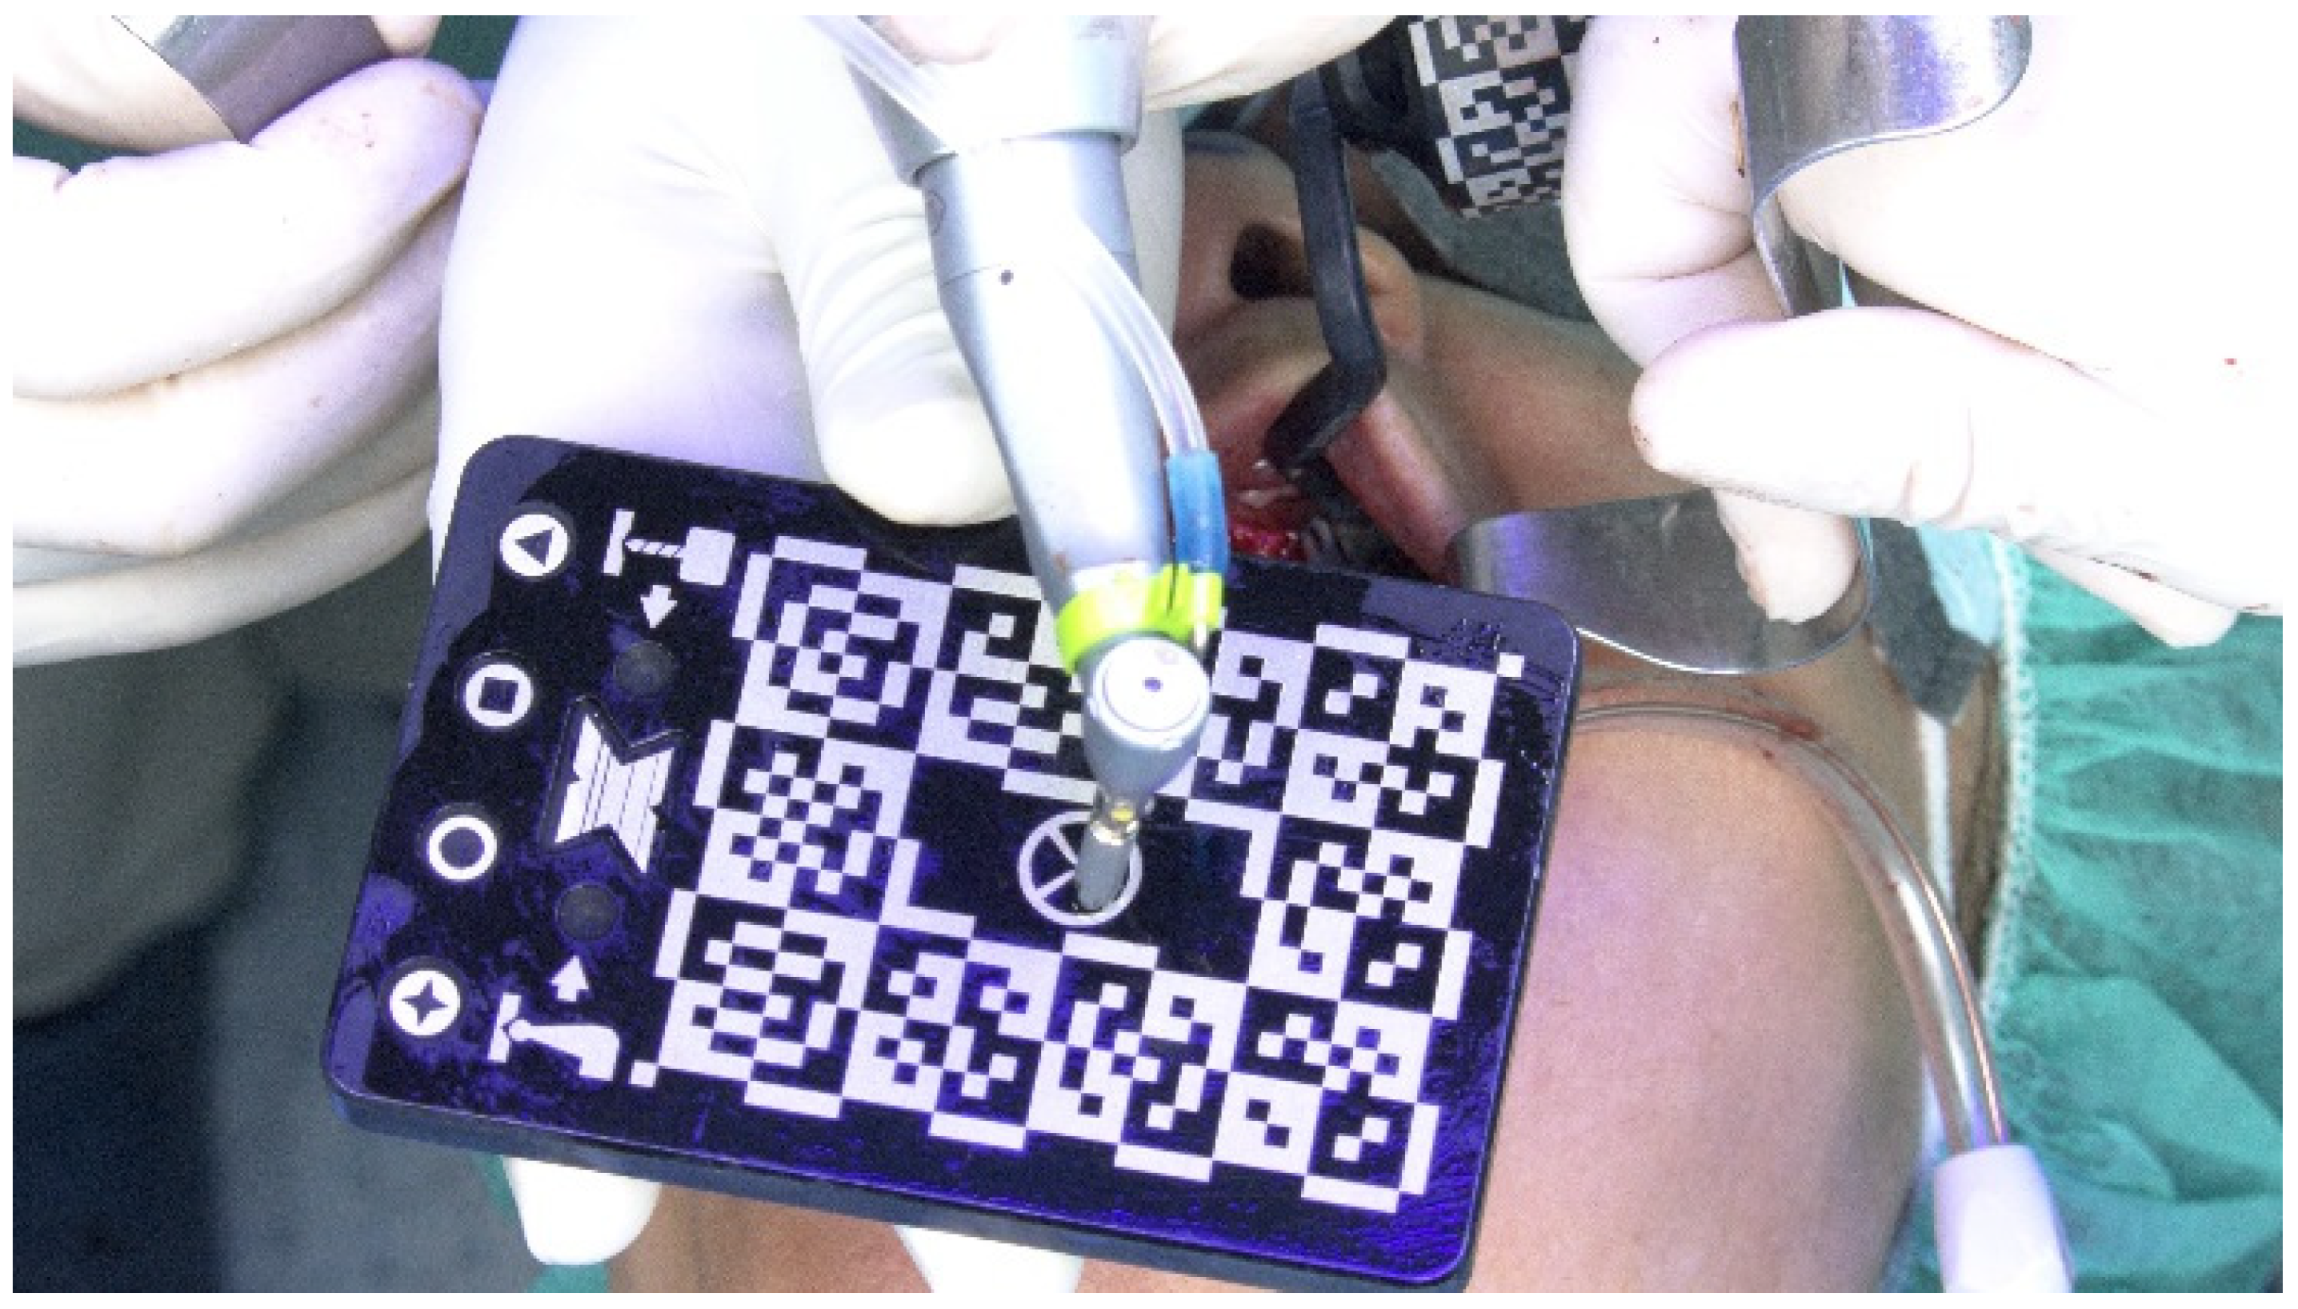

Calibration In Dynamic Navigation Surgery In Implamt

Browse our specialized Calibration In Dynamic Navigation Surgery In Implamt portfolio with numerous expertly curated photographs. optimized for both digital and print applications across multiple platforms. providing reliable visual resources for business and academic use. Each Calibration In Dynamic Navigation Surgery In Implamt image is carefully selected for superior visual impact and professional quality. Perfect for marketing materials, corporate presentations, advertising campaigns, and professional publications All Calibration In Dynamic Navigation Surgery In Implamt images are available in high resolution with professional-grade quality, optimized for both digital and print applications, and include comprehensive metadata for easy organization and usage. Our Calibration In Dynamic Navigation Surgery In Implamt collection provides reliable visual resources for business presentations and marketing materials. Whether for commercial projects or personal use, our Calibration In Dynamic Navigation Surgery In Implamt collection delivers consistent excellence. The Calibration In Dynamic Navigation Surgery In Implamt archive serves professionals, educators, and creatives across diverse industries. Regular updates keep the Calibration In Dynamic Navigation Surgery In Implamt collection current with contemporary trends and styles. Advanced search capabilities make finding the perfect Calibration In Dynamic Navigation Surgery In Implamt image effortless and efficient. Multiple resolution options ensure optimal performance across different platforms and applications.